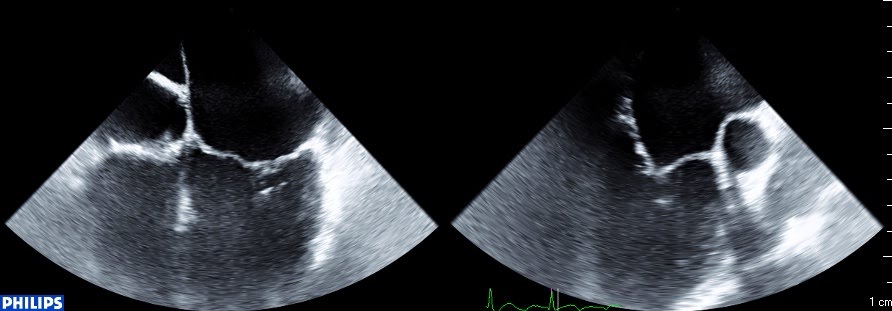

En 3d, (vue "chirurgicale" de l'oreillette gauche habituelle, aorte en haut, auricule à droite) on est d'emblée frappé par la déformation de l'anneau, qui semble aplati sur la commissure antérieure.

La valve ferme au milieu, mais les deux commissures (et surtout l'antérieure) restent ouvertes (et donc fuyantes).

Systole (noter l'absence de coaptation dans les zones commissurales):